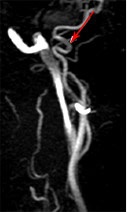

Patológiai zegzugosságát (megtörését) a nyaki artéria egyik legkevésbé megértett és rejtélyes betegség. A szerepe a kóros tekervényességének cerebrovascularis elégtelenség tünete fejlesztés még tanulmányozzák, de úgy találta, hogy az egyik a három halt meg agyvérzés találtak kóros görbék a nyaki vagy a csigolya artériák. A 16-26% a felnőtt lakosság azonosított különböző lehetőségeket hosszabbítás és tekervényességének a nyaki csigolya artériák vagy a nyakon. Megtörését - Ez az egyenetlenség az artéria alkotnak ívek, hurkok és csomók, amelyek befolyásolják a természet véráramlás az artériákban és hozzájárulnak a stroke.

Gubancold mindig fejlődik, mert a kiterjesztése a belső nyaki verőér, amely arra kényszerítette alakul csavarják vagy hurkok. A fölös hossza arteria carotis interna gyakran meghatározott időszakban az embrionális fejlődés, azaz artéria kanyargás gyakran veleszületett. Az életkor, a további szigorítása feleslegben arteria carotis hurok előfordulhat. Egyes kutatók szerint gubancold okozhat neurológiai és mentális problémák a gyermekek óvodai és a korai iskolás korú.

Diagnózis patológiás tekervényességének

Tekintettel a széles körű terjesztése a különböző típusú jogsértések alkotják a nyaki artériák, az orvos-nek pontosan megválaszolni a kérdést -, hogy egy ilyen változás alakja az artéria megtörés vagy nem? A válasz erre a kérdésre lehetővé teszi, hogy meghatározza, hogy szükség van a sebészeti beavatkozást. Diagnosztikai algoritmus alapján a következő séma szerint:

Ha azt állapítjuk meg, hogy a tekervényes artéria felgyorsult áramlás a ponton a hajlító, hogy több, mint 2-szer, ahol a beteg tünetei cerebrovaszkuláris megerősítette érrendszeri elváltozások az agyban anyag oldalán bodros haj, mint hullámok elismert patológiás és figyelemmel a sebészeti korrekciót.